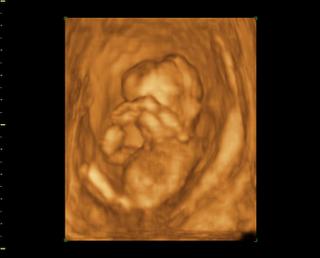

Tak čaute kočky, som doma z 3Dčka, dnes som 14+1 mám plno krásnych fotiek na kľúči, najbližšie mám prísť na 3Dčko v 20tt a potom tretí krát okolo 25 tt a vtedy dostanem aj DVDčko zo všetkých troch UV. Ale fotky aj videá nám dal na USB kľúč takže už teraz mám všetky 🙂 Čo sa pohlavia týka, tak to vyzerá na chlapca, ešte mám aj jednu fotku kde to zreteľne vidieť že to bude asi chlapec. bábo bolo aktívne strašne veľa skákalo a pohybovalo sa, stále si rúčkami chytalo hlavičku (to robí aj Danko stále 😀 ) Priateľ bol vnútri so mnou takže to celé videl.